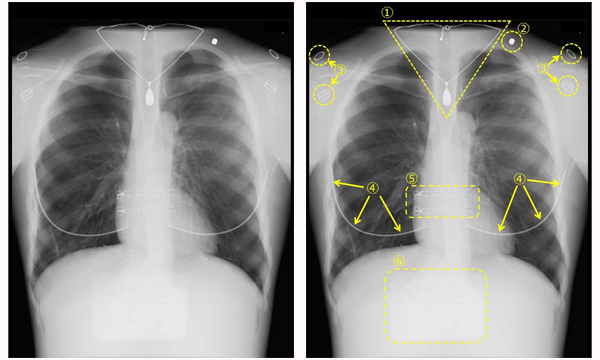

金属類などが写り込んでいる胸部X線写真の例

①ネックレス ②エレキバン(磁石) ③下着の金具 ④下着のワイヤー ⑤下着のホック ⑥カイロ